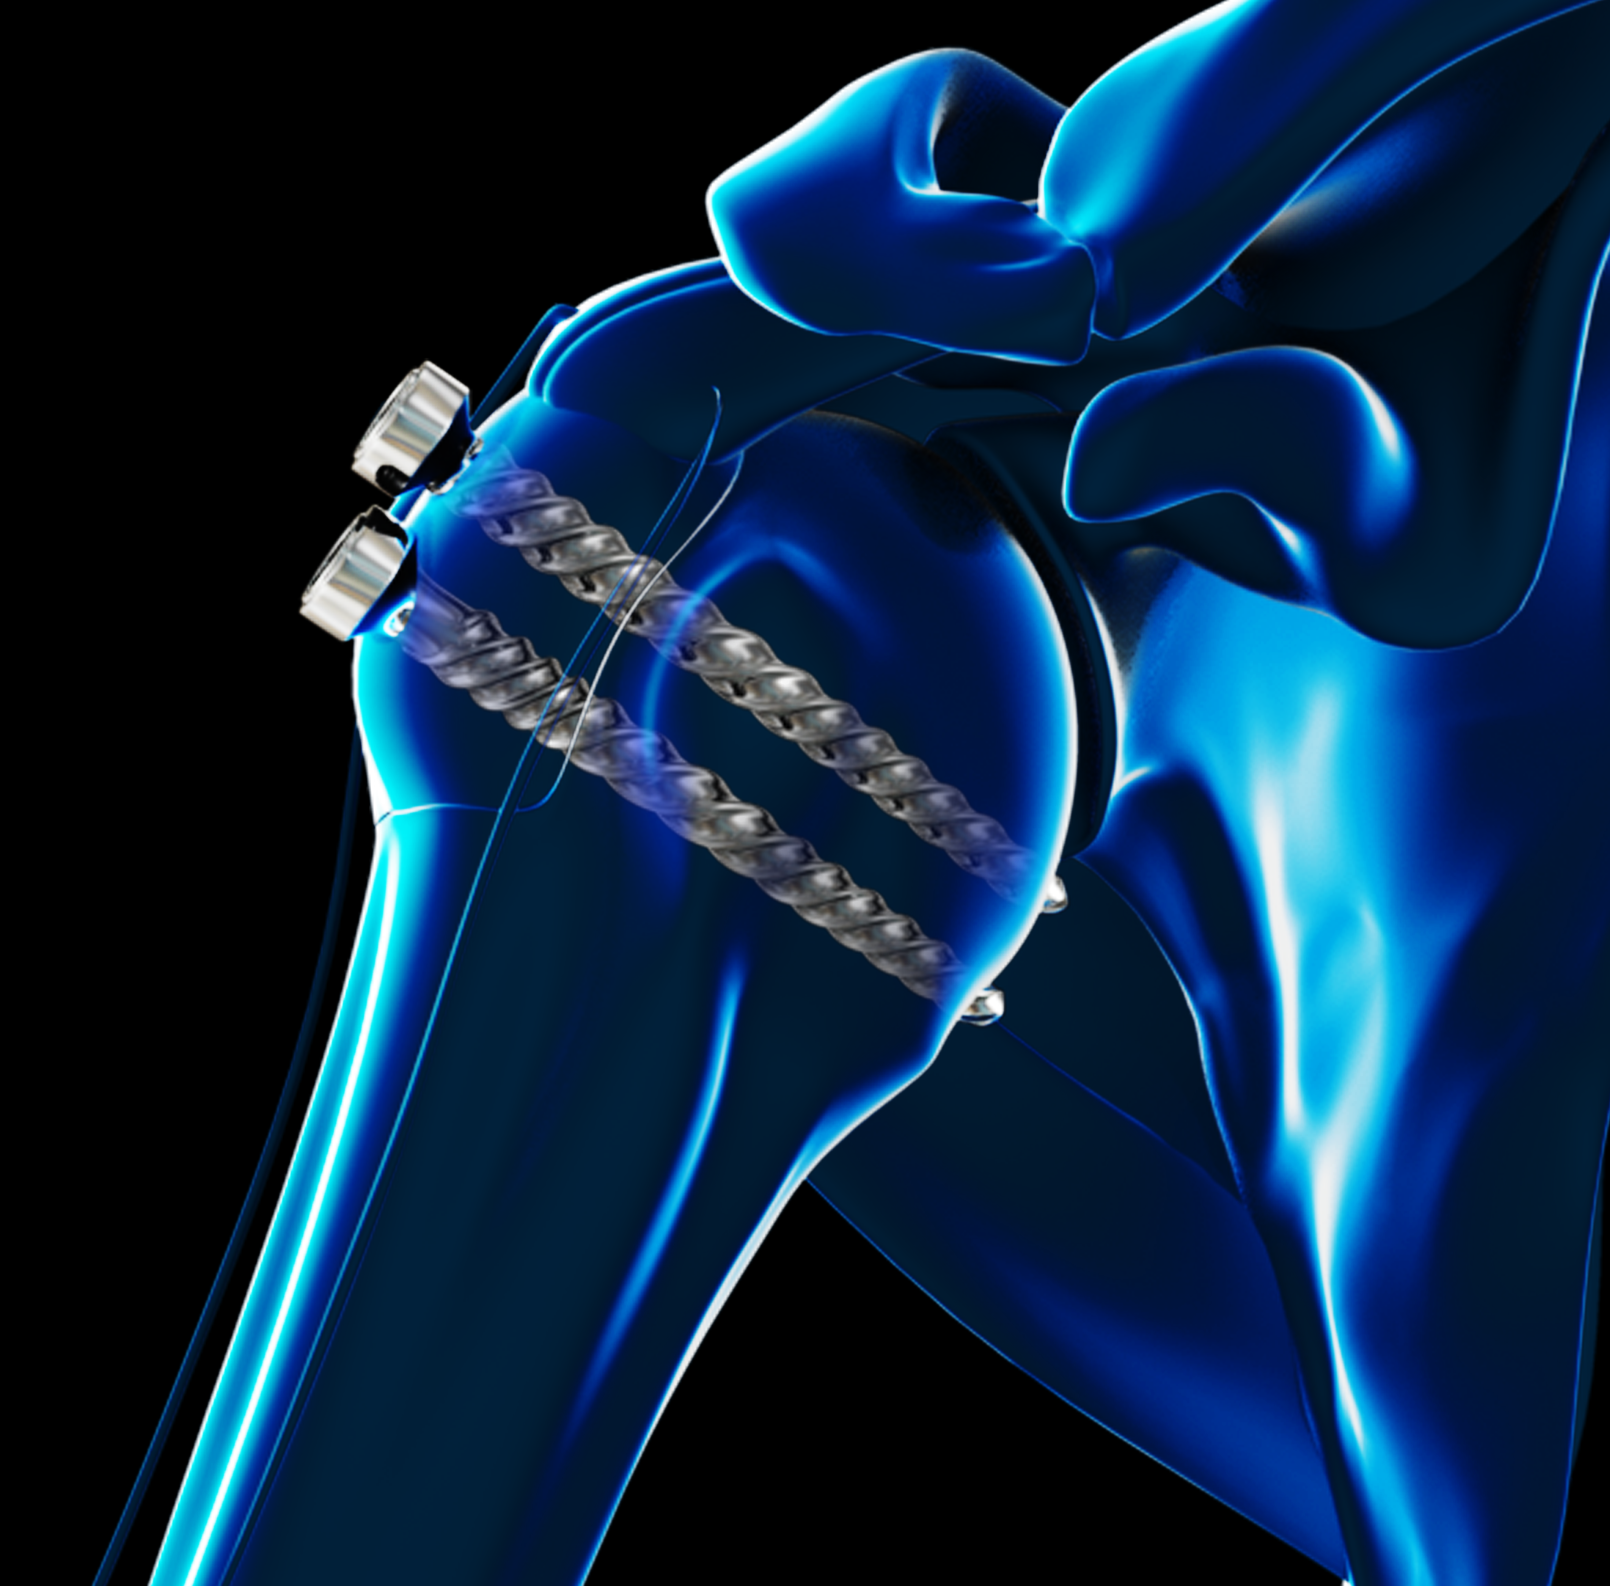

ORIF Proximal Humerus Fracture

Open reduction and internal fixation (ORIF) is a surgical technique employed for the treatment of fractures to restore the normal anatomy of the bone.